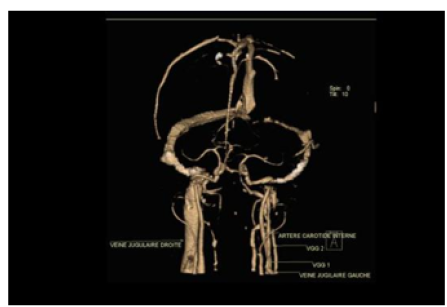

Internal Jugular Vein Duplication: Case Report

N Amsiguine, S Habib Chorfa, J El Mandour, A Lahfidi, F Touarssa, M Fikri, N Elkettani and M Jiddane. 15(6): 25-27.